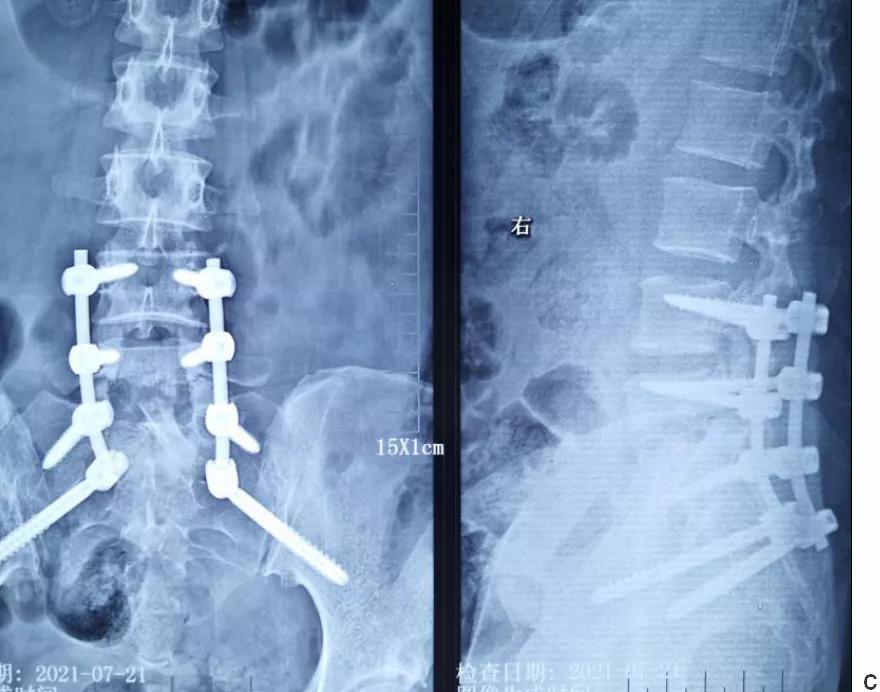

术后影像学检查

a.术后髂翼位置示双侧S2AI钉位置良好。

b.术后正侧位片示腰4/5/骶1螺钉位置良好。

c.前路植骨术后正侧位片示腰4/5/骶1螺钉位置良好,腰5-骶1椎间植骨(自体髂骨三层皮质骨)位置良好。